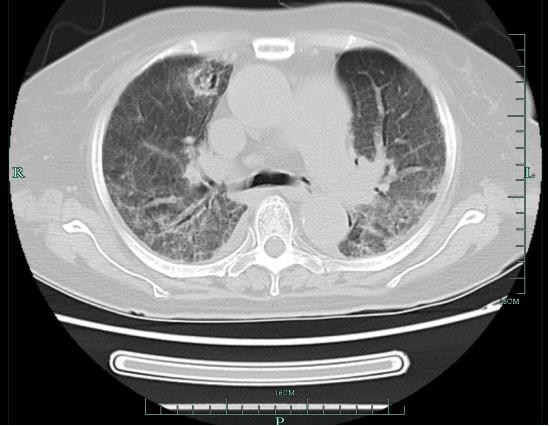

看过杨女士的肺部CT后 , 接诊医生有了初步判断 , 但同时也心生疑惑:杨女士每经过一次治疗体温都会暂时回归正常 , 可能还合并有其他病原体的感染 。

进一步的检验证实了医生的疑惑 。 杨女士感染曲霉菌诊断明确 , 同时血培养提示草绿色链球菌 , 这是一种口腔定植菌 , 也就是说每个人的口腔内都有这种细菌 , 正常情况下它对人体并无大害 , 但如若进入血管内 , 有可能导致细菌性心内膜炎 。